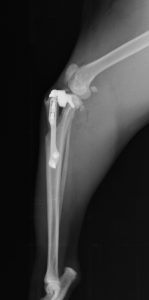

TTA

膝蓋骨靭帯の付着部(脛骨粗面)を骨きりして前方に持ち上げることで、大腿部の筋肉(大腿四頭筋)の角度を変え、大腿四頭筋群の作用によって正常な関節の動きを再現します。専用のTTAプレートと脛骨粗面を持ち上げておくためのケージを設置します。

32kg ラブラドール